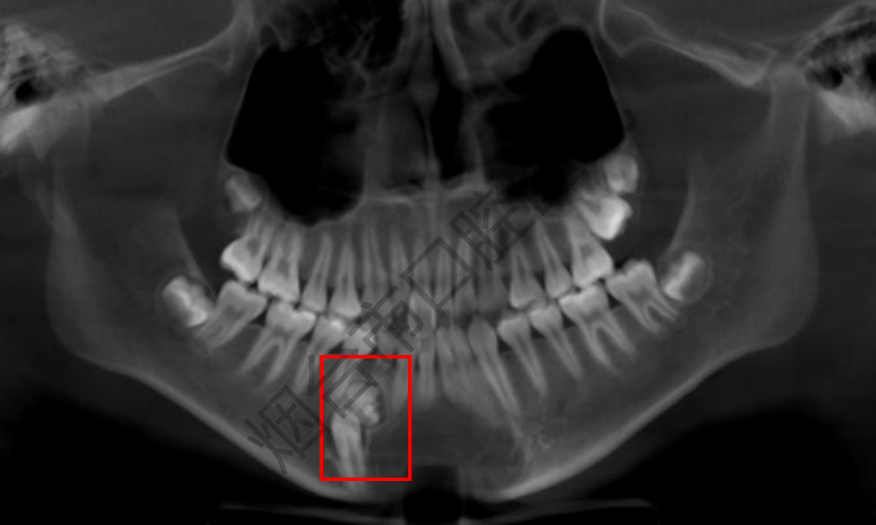

近日,12岁的男孩林林(化名)因为要做牙齿正畸来到烟台市口腔医院就诊。医生在常规检查时发现,他右下颌的一颗乳牙迟迟没退,属于乳牙滞留的情况。为了查清楚原因,医生安排他做了CBCT检查,这一查竟发现了大问题—— 林林的颌骨里藏着一个边界清晰的“团块”,里面密密麻麻裹着十几颗形态各异的“小牙”。

据了解,林林在此前一个月内并未感到任何疼痛或不适,这个“藏”在骨头里的“小麻烦”,全靠检查才被发现。结合检查结果,医生初步判断这是“牙瘤”,随后安排林林住院治疗。

很多人看到“瘤”字会心生恐惧,烟台市口腔医院口腔颌面外科病房主任孙超介绍,牙瘤并非癌症,而是一种起源于牙胚组织的良性肿瘤。它由牙齿发育过程中残留的细胞异常增生、钙化形成,形态上既可能是一团混乱的钙化团块,也可能是数十颗形态近似正常但体积微小的牙齿堆积而成。其病因通常认为与牙胚发育异常、遗传因素等相关。

孙超提醒,早期牙瘤通常无明显症状,多在拍摄X 光片时偶然发现。随着肿瘤逐渐增大,可能引发颌骨局部肿胀隐痛、阻碍恒牙萌出导致乳牙滞留、牙齿移位、咬合紊乱,甚至压迫神经引发面部麻木疼痛、继发感染出现牙龈红肿流脓等问题。因此,定期进行口腔检查,尤其在儿童替牙期和正畸前开展影像学筛查,对于早期发现和处理牙瘤至关重要。一旦确诊,手术切除是唯一有效的治疗方法。